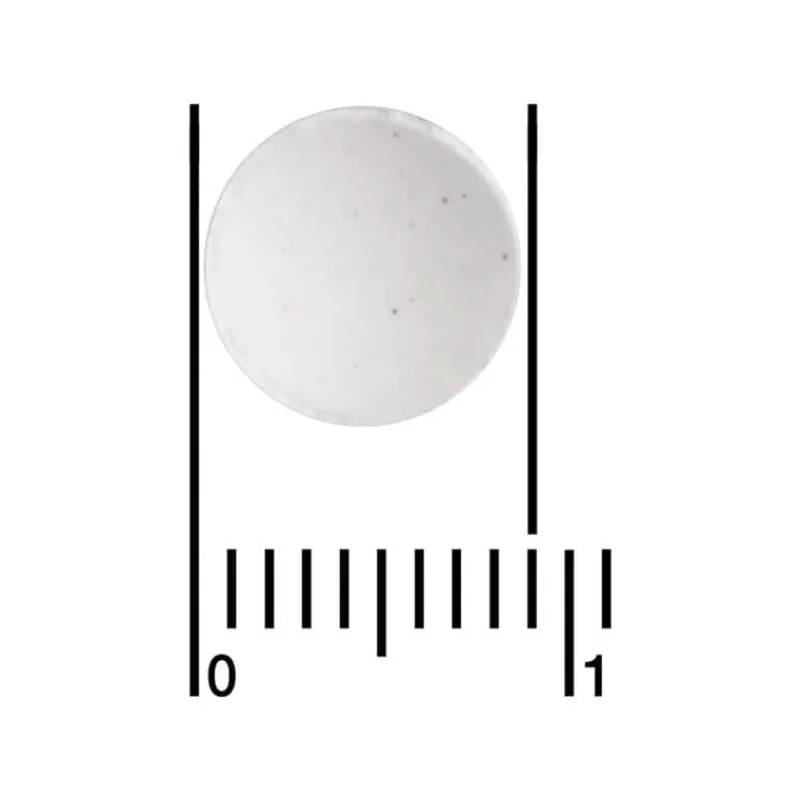

tabletten